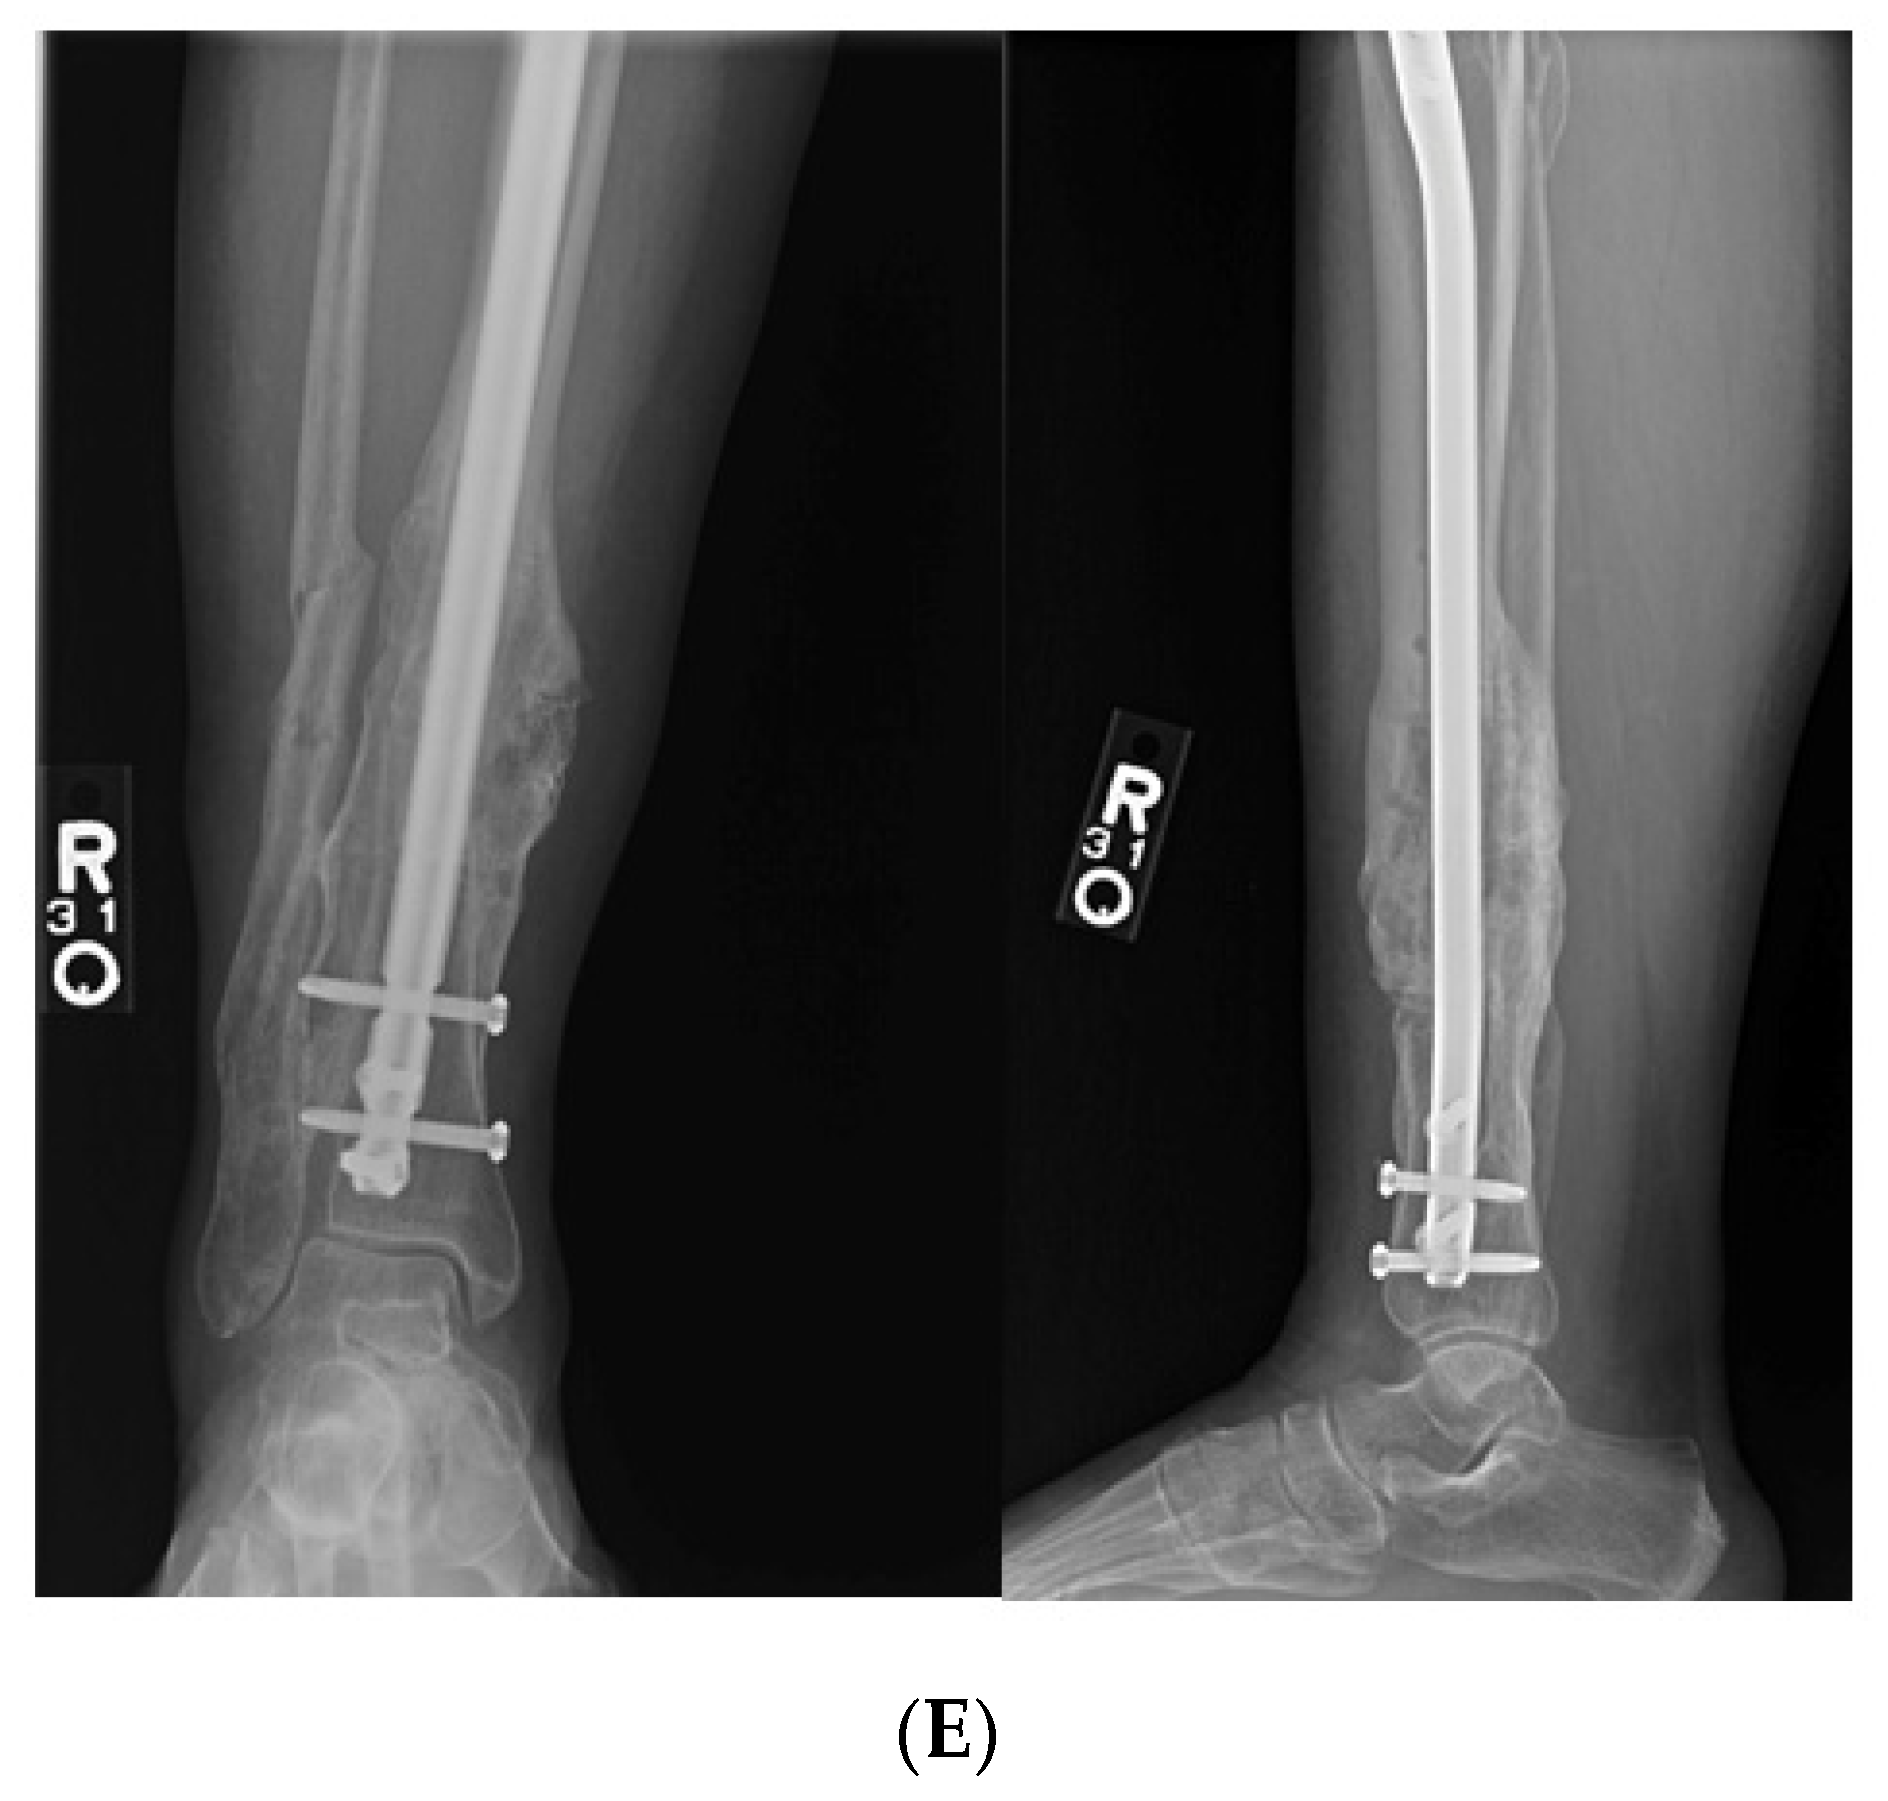

9.3. Case 3

A middle-aged female was treated at an outside hospital for a distal quarter tibia fracture with a concomitant lateral malleolus fracture. She was treated with an intramedullary tibial nail with only proximal interlocking. She was allowed early weight bearing after surgical fixation. She subsequently developed a valgus malunion. She was referred to our facility for deformity correction two years after her initial surgery. She complained of pain with any weight bearing and she utilized a cane for assistance with ambulation. Her past medical history was significant for diabetic neuropathy and hypertension. Her physical exam was remarkable for a resting valgus posture of the tibia that was more pronounced with weight bearing. Her prior incisions for her first surgery were well healed, and there were not any traumatic wounds or incisions where either approach for the clamshell osteotomy could be performed. Her distal tibial valgus deformity measured 16° with shortening. She opted for surgical intervention to correct her tibial malunion. A clamshell osteotomy was performed after removal of her initial tibial intramedullary nail (Figure 6). In addition, a fibular osteotomy and a medially based universal distractor were used to assist with the tibial deformity correction. A posteromedial approach was performed to expose her malunion. She went on to heal her osteotomy without any postoperative complications.

Figure 6. (A): AP and lateral tibial XR demonstrating failure of tibial nail with valgus malunion. Notice there are not any distal interlocking screws. (B): Intraoperative fluoro views demonstrating medial universal distractor being used to assist with deformity correction, and maintain alignment during intramedullary nailing. (C): Intraoperative views demonstrating tibial nail and fibular plate after clamshell and fibular osteotomies. (D): AP and lateral 3-month post operative follow up XRs demonstrating healed clamshell osteotomy.